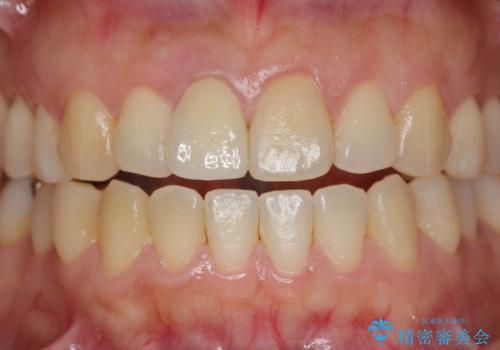

オーダーメイドで造る、自然な前歯セラミッククラウン

- 幼少期に前歯をぶつけて歯が折れ、神経の治療・クラウン治療を行った。グラつきと見た目の改善を希望して来院されました。

精密な仮歯をいれ、歯周組織を整えるとともにファイバーコア築盛、シェードテイキングを行い見た目に自然なジルコニアクラウンを製作していきます。

ジルコニアクラウンの中でも当法人のグレードの高い、スペシャル・エクセレントプランはオーダーメイドで色調を合わせることで周囲の歯に馴染んだ自然な歯を製作することのできるプランです。